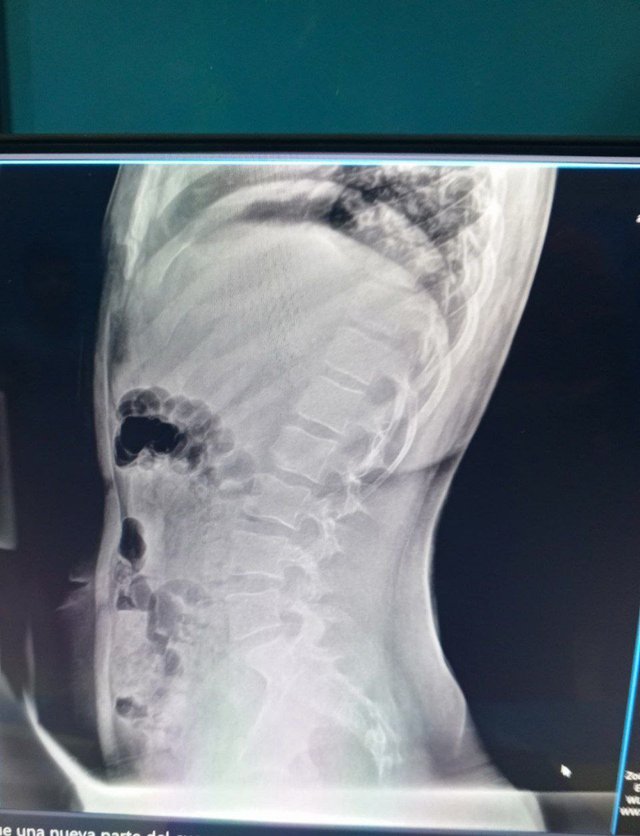

En esta primera semana, vengo con un paciente masculino de 14 años con escoliosis lumbar. Él tiene un historial médico con antecedentes genéticos de escoliosis y dolor durante la infancia que afectaba una pierna sin agnóstico. Acá dejo los rayos X.

El diagnóstico definitivo del paciente fue en 2024, cuando acudió a consulta a los 13 años debido a un dolor lumbar crónico a raíz de un accidente automovilístico, en el cual recibió parte importante del impacto. Fue tratado con tiocolchicósido e ibuprofeno, también requirió del uso de un corsé.

Task 2 (2.5/2.5)Yes, before reading your post I guessed through X ray that it's scoliosis, that's sad it's genetic scoliosis and even in so early age. But now there are advance treatment option for scoliosis other than physiotherapy. Scoliosis happens like there will be tightness of muscles in one side and weakness in other side. So, the best thing is using orthosis or prothesis with physiotherapy management.